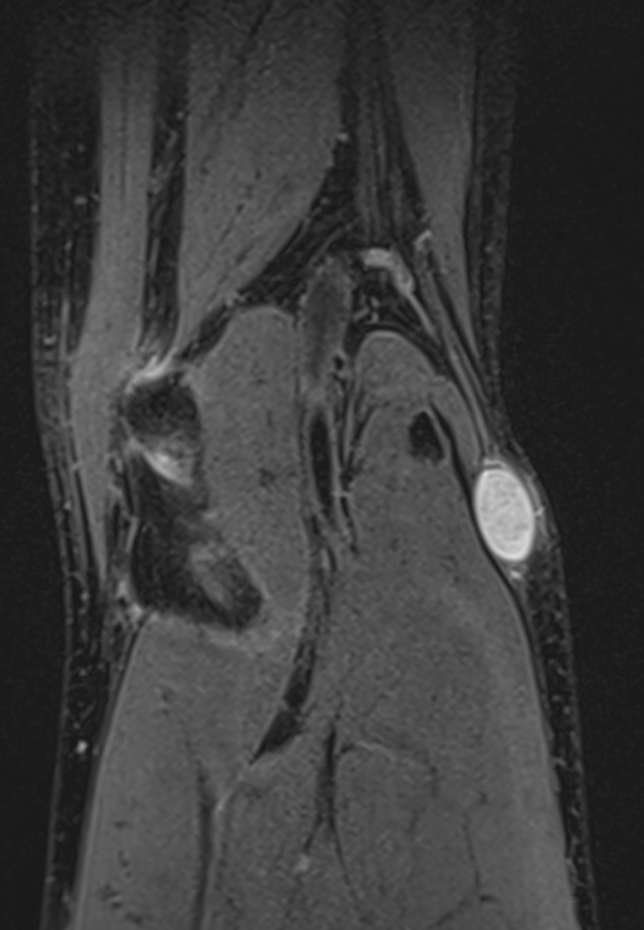

MRI

Target sign

- hypointense centrally

- hyperintense peripherally

Neurofibroma common peroneal nerve